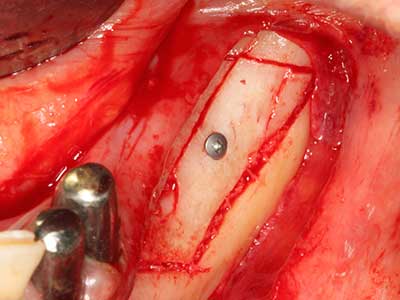

Костната тъкан е не само минерализирана структура, тя съдържа и съществено количество колагенови влакна. Това означава, че тя има не само добра компресивна сила, но и известна степен на гъвкавост, която може да се възприеме като предимство при извършване на костна аугментация. В класическата процедура по разширяване чрез костно разделяне, атрофиралият алвеоларен гребен е разделен надлъжно и внимателно разширен след достигане на подходящата остеотомна дълбочина (Фиг. 13-16), в идеалния случай без допълнително отстраняване на периостеума (Brugnami, Caiazzo et al. 2014, Stricker, Fleiner et al. 2014). Системите с винт и пластини с увеличаване на разстоянието при разширяване са доказали ефективността си при разделяне на двете костни ламели, оставайки под прага на фрактурите. В общи линии, оставащата ширина на костта от поне 3–4 mm е задължителна (Chiapasco, Zaniboni et al. 2006), за да се гарантира добра гъвкавост и достатъчно костно покритие за бъдещото поставяне на импланти. Ако е необходимо, вертикалната остеотомия на едната или двете страни може да подобри гъвкавостта. Комбинацията с допълнителни техники за аугментация, особено в букалната страна, е описана като алтернатива на класическата техника.

Процедурата по разделяне е атравматична и няма голяма загуба на пространство, използвайки пиезотриони, и няма значителна разлика между импланти в разделени челюсти и импланти в алвеоларния гребен без костен дефицит (Chiapasco, Zaniboni et al. 2006, Danza, Guidi et al. 2009). Въпреки това, важно е да има достатъчно и продължително охлаждане, особено при ограничено и дълбоко разделяне, за да се избегне термичен стрес в апикално-остеотомните зони.